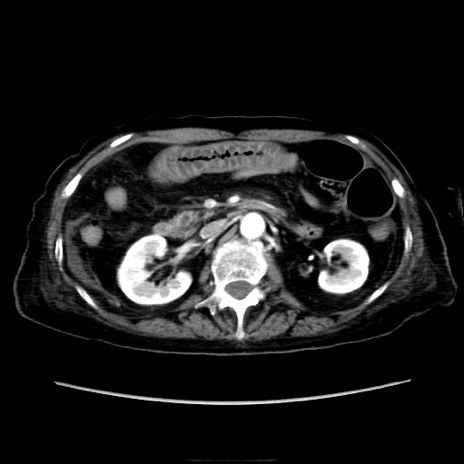

症例40(横断像)

【症例】90歳代女性

【主訴】腹痛・嘔吐

【現病歴】 食欲低下、嘔吐があり昨日他院受診。肺炎と診断され入院となる。入院後より腹部全体に圧痛あり。胃管留置され経過みていたが、症状持続するため、

当院転院となる。

【既往歴】胸椎圧迫骨折、胆石症

【身体所見】腹部:中央に激痛あり、圧痛あり、反跳痛不明

【データ】WBC 17100、CRP 18.82

横断像